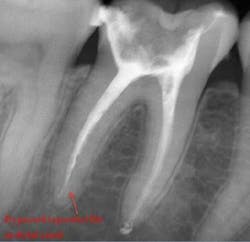

Once all of the canals are found, I will go through the series of Sybron Twisted Files size 25 tapering from 0.10 to 0.80 to 0.60 to 0.40. The 0.40 file should reach the working length for most canals. On a large palatal or distal canal, the 0.60 TF will usually reach working length. After which, using the crown-down technique with the Brasseler EndoSequence rotary files, instrument each canal until files reach the working length. Once instrumentation is complete, take a P.A. with gutta-percha to confirm instrumentation to working length. I find it much easier to take working length films with gutta-percha rather than files (which may fall out, bend, or separate)